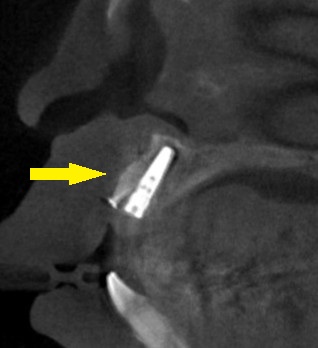

それでも、抜歯して、2~3か月後の早めの時期に、インプラント埋入と同時に、人工骨を用いた骨造成術を併用して行うことで、インプラント治療が可能であると説明させていただきました。

患者様の同意が得られましたので、本日、予定どおりの手術を施行しました。

下の写真3段目が手術後のCTとなります。